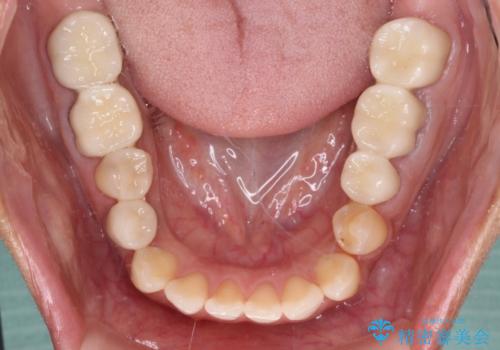

歯を削る量は増えますが、より長い期間再治療なく使用していただくことを最優先に考え、フルカバレッジのオールセラミックブリッジにて補綴することとしました。

我々としては、治療により状態が悪化することだけは避けたいと考えているため、歯全体を覆うクラウンにすることで、より長持ちする治療を提供いたしました。

外観はもちろんのこと、隙間なく安心して咬むことのできる前歯となり、患者様には大変満足していただきました。